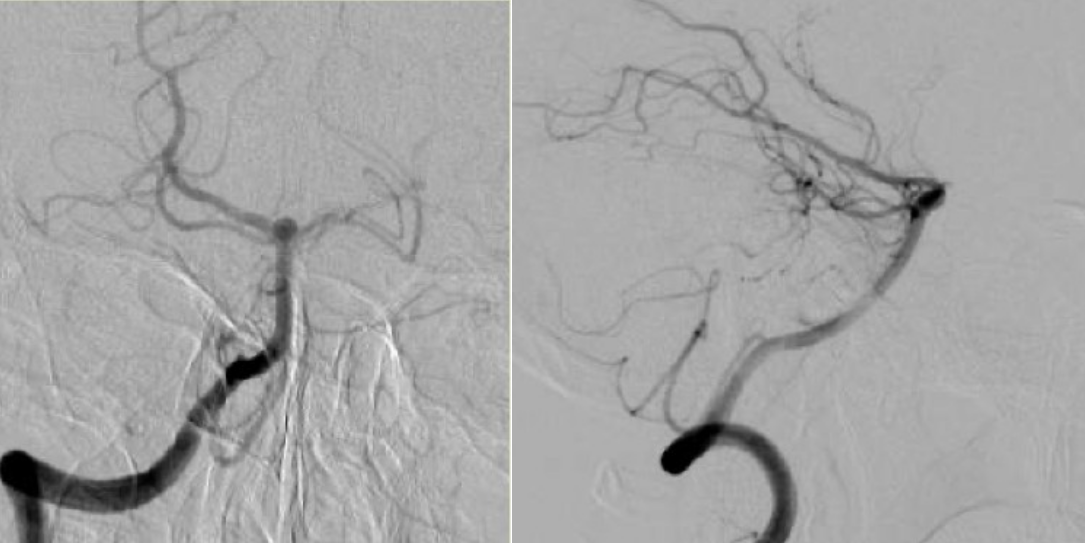

右侧椎动脉造影示基底动脉瘤。

椎动脉造影(放大图像)示基底动脉瘤。

椎动脉侧位造影(放大图像)示基底动脉瘤。